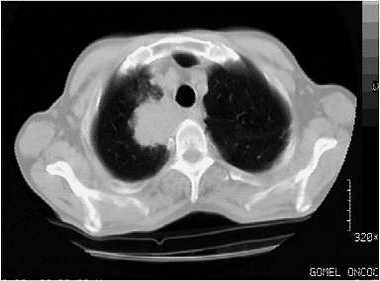

Методика исследования: обследование больного проводят в горизонтальном положении на спине, при задержанном вдохе. Толщина среза 8 мм, шаг томографии 8-16 мм, при уточнении изменений эти параметры уменьшаются. Зону сканирования выбирают в зависимости от распространенности процесса по топограмме в прямой проекции, исследование обычно начинают от уровня яремной ямки.

На томограммах определяются легочная паренхима, элементы средостения, мягкие ткани и ребра грудной стенки. Поскольку они имеют разные показатели коэффициента поглощения, резко отличающиеся друг от друга, каждый срез необходимо просматривать на двух режимах: (окна 520-1000 и 120-300). Наличие режима "двух окон" позволяет одновременно оценивать все структуры на срезе.

К-Т картина периферического рака легкого характеризуется такими же признаками, как и в традиционной рентгенодиагностике: образование неправильной округлой формы с нечеткими неровными контурами. Эти отличия периферического рака от доброкачественных образований и метастазов проявляются в виде широкой (более 3-4 мм) зоны увеличения плотности вокруг опухоли (от - 550 до - 250 ед. Н), а плотность самой злокачественной опухоли расположена в диапазоне от +30 до + 60 ед.Н. КТ позволяет выявить возможный распад опухоли с образованием полости при пересмотре срезов на более низком "окне" (Приложение А рисунок 5). При помощи КТ удается обнаружить и явления регионарного лимфангита в виде "дорожки" между корнем легкого и опухолью. В отличие от сосудов "дорожка" уменьшается по ширине от образования к корню легкого.

К-Т исследование позволяет изучить взаимоотношение между периферическим раком и органами средостения, а также элементами грудной стенки.

Прорастание опухоли проявляется, в первую очередь, в том, что:

а) опухоль локализуется как в легком, так и в средостении с вовлечением в процесс крупных сосудистых структур;

б) между опухолью, средостением и плеврой отсутствует жировая клетчатка;

в) имеется наличие жидкости в полости перикарда и утолщение его стенки;

г) при непосредственной близости опухоли к плевре последняя утолщена и подтянута к узлу.

Увеличенные свыше 10 мм лимфоузлы, что указывает на их метастазирование, особенно в области бифуркации трахеи и легочных корней, имеют тенденцию к слиянию. В то же время в неувеличенных лимфоузлах в 20-25% случаев выявляются скрытые метастазы рака легкого.

Исходя из этих данных, степени операбельности рака легкого при КТ исследовании определяют по таким признакам: вовлечение в опухолевый процесс смежных элементов средостения (перикарда, верхней полой вены), а также плевры и других структур грудной стенки (Приложение А рисунок 6). Метастатическое поражение лимфоузлов средостения.